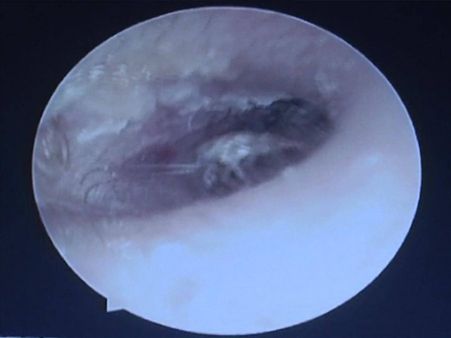

Case Of 26 Cockroaches That Were Breeding In A Man's Ear

Real-life Story: When 26 Cockroaches Were Found In A Man's Ear!

A human body cannot tolerate any foreign object inside it. Be it a prick or a nail, the body tremors with pain and rejection.

With such sensitivity, can you imagine of having any insect dwelling in any of the body parts? It sounds creepy, but there are several such cases that have been reported of insects found in human bodies.

A recent bizarre case was reported in China, where doctors found 26 live cockroaches alive in a man's ear!

The Man Complained Of Ear Ache…

The unnamed man had been complaining of ear pain for a while, until he decided to pay a visit to the doctor, as he had a constant wiggling feeling in his ear. The pain had left him with little sensation to hear sounds.

When Examined…

When the doctors examined, they found something looking back at them. They instantly had to take an action, as they assumed an insect to be resting in his ear. He was examined and the doctors got a shock of their lives when they discovered a cockroach family dwelling in his ear.

He Was Immediately Operated…

The unnamed man was given anesthesia and the doctors started pulling out the cockroaches one by one from his ear. The total number at the end of the surgery was 26 cockroaches! The worst thing about this case was that all the 26 cockroaches were alive and active!

It Was A Female Cockroach That Had Done The Damage

The doctors revealed that they found 0.3-inch-long cockroach which had got inside the man's ear and had laid the egg. The warm temperature of the ear was perfect for the egg to hatch and hence all the young ones were alive.

A Little More About The Cockroaches...

According to the studies, a female cockroach is said to carry a capsule that contains around 40 eggs, which develop into adults in a span of three to four months' time. The man was lucky enough that he did not wait for so long!

The Doctors Revealed…

After the surgery, the doctors revealed that if the man had not come to the hospital at the right time, his ear would have probably been "destroyed".